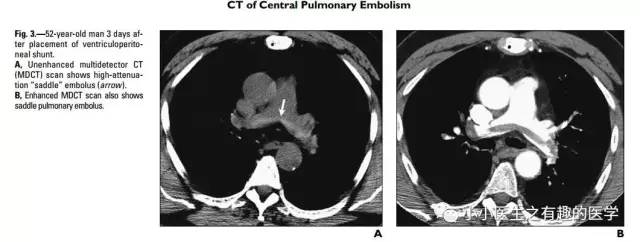

病例介绍三:

国外有高手专门研究了CT平扫诊断肺栓塞的可靠程度。

高分辨CT平扫管腔内高密度征象诊断肺栓塞的敏感性36.0%, 特异性99.0%, 阳性预测值90.0%, 阴性预测值85.6% 。

阴沟里洗原文:The hyperdense lumen sign has an over-all sensitivity of 36.0%, specificity of 99.0%, PPV of 90.0%, and NPV of 85.6% (κ = 0.449; P-value < 0.001).

高分辨CT平扫管腔内高密度征象诊断中心肺栓塞敏感性66.7%, 特异性99.1%。

阴沟里洗原文: In detecting central thromboembolism, the sensitivity, specificity, PPV, and NPV of this sign were 66.7, 99.1, 88.9, and 96.4%, respectively (κ = 0.740; P-value < 0.001).